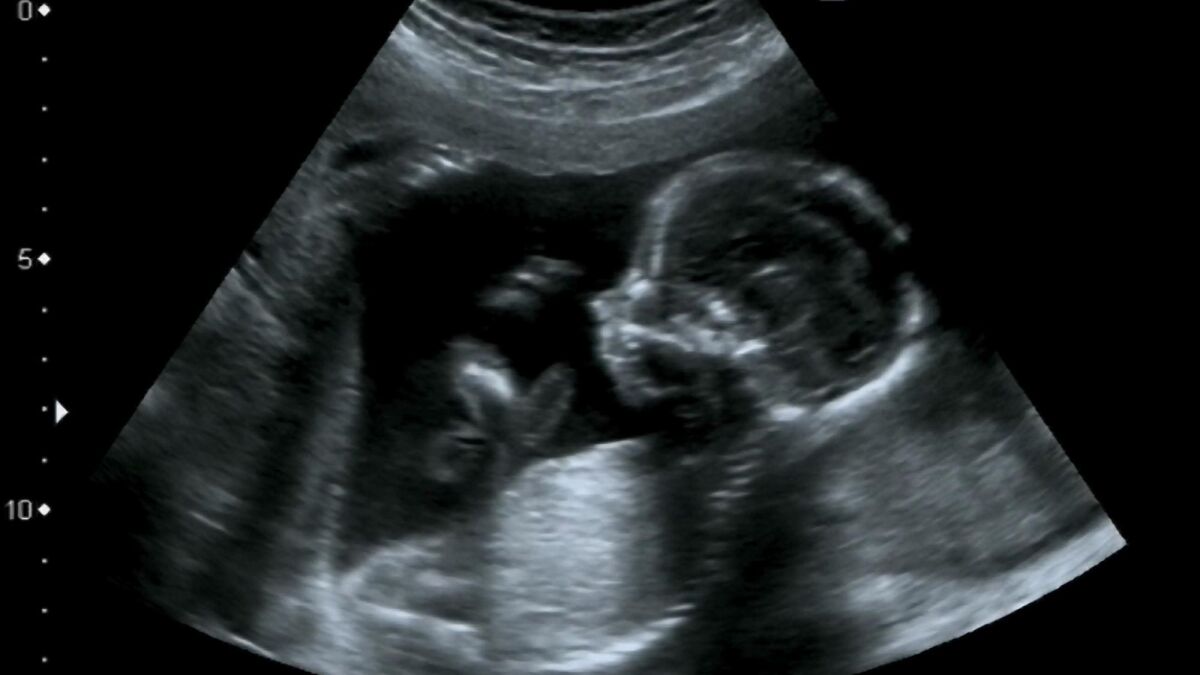

Según han publicado varios medios del país asiático, el robot tiene forma humanoide y está equipado con un útero artificial en el abdomen, lo que permite la gestación de un feto humano durante las 40 semanas de embarazo y posteriormente dar a luz.

En una entrevista en la revista Kuai Ke Zhi, Zhang Qifeng, fundador de la empresa Kaiwa Technology, aseguró que el "robot de embarazo" no es una incubadora, sino un humanoide con un útero artificial que puede replicar todo el proceso natural de un embarazo, desde la concepción hasta el parto.

Según ha asegurado, este útero artificial ya se encuentra en una etapa avanzado y sería necesario implantarla en el robot para que un humano interactúe con él y se logre el embarazo. Todavía no se ha revelado cómo se fecunda el óvulo ni cómo llega el espermatozoide al útero artificial.

Una vez "embarazado" el robot será capaz de que el feto crezca en su interior. Al parecer, el útero estaría lleno de líquido amniótico artificial y el bebé sería alimentado a través de una sonda.